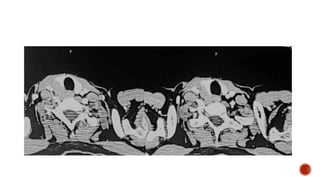

 Scout film shows enlarged renal shadows

 Full bladder image shows a well distended urinary bladder with multiple broad

based diverticulae and wall irregularities.

 On straining there is no vesicoureteric reflux.

 Trauma

 Multiple sclerosis

 Parkinson disease

 Cauda equina syndrome

 Neuritis

 Sensory : Inability to sense bladder fullness results in a large rounded and smooth

bladder. Voiding is often preserved.

 Motor : Atonic large bladder with the inability of detrusor contraction during

voiding.

 Reflex/uninhibited : Lesions above S2 level (Christmas tree/pine cone appearance)

 Self catheterization

 Prevent complications

 Bladder training

 Cystoplasty

 Neuromodulation

 Non-neurogenic neurogenic bladder